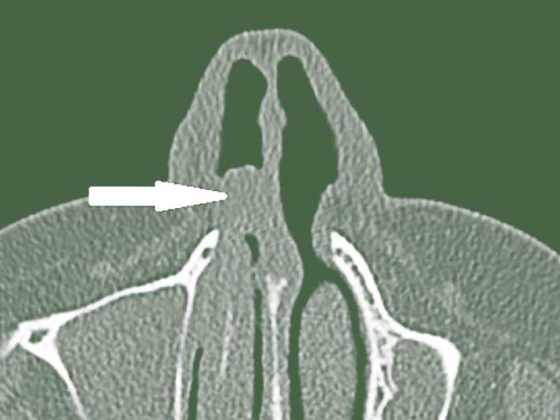

header_nasenkrebs

• Schleimhautmelanome im Kopf- und Halsbereich

Seltener, aber aggressiver als kutane Melanome